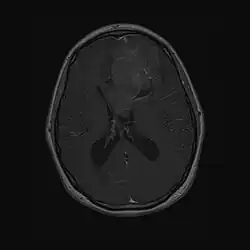

Als Neurozytom wird ein seltener gutartiger Hirntumor bezeichnet. Da Rezidive auftreten können, wird der Tumor nach der WHO-Klassifikation der Tumoren des zentralen Nervensystems als Grad II eingeordnet. Die WHO-Klassifikation unterscheidet das typischerweise intraventrikulär im Bereich des Foramen Monroi gelegene zentrale Neurozytom vom selteneren extraventrikulären Neurozytom, das keinen Bezug zum Ventrikelsystem des Gehirns besitzt.

Neurozytome sind selten. Seit der Erstbeschreibung im Jahre 1982[1] sind weltweit einige 100 Fälle berichtet worden. Das zentrale Neurozytom führt aufgrund seiner intraventrikulären Lage typischerweise zu einer Behinderung des Liquorabflusses und macht sich klinisch als Hydrocephalus bemerkbar. In der Bildgebung stellen sich Neurozytome als nicht selten zystische, variabel Kontrastmittel aufnehmende Raumforderungen dar.